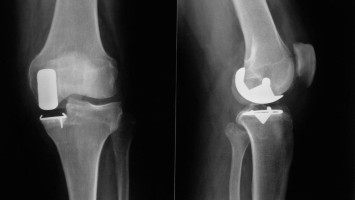

Knie-TEP: Bei wem ist das Risiko für Instabilität erhöht?

Warum kommt es nach einer Knie-TEP manchmal zu Instabilität? Hamburger Orthopäden sind dieser Frage retrospektiv nachgegangen. Ihre Ergebnisse werfen neue Fragen für die Praxis auf.